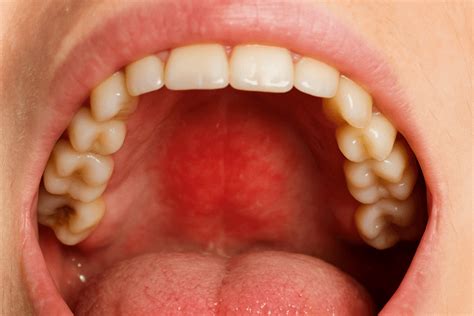

Inflamación del Paladar: Causas y Tratamientos

Los dientes, la lengua y las encías no son los únicos elementos que pueden presentar dolencias que afectan la salud bucodental. También es importante que prestes atención a otras zonas menos comunes. La inflamación del paladar es una condición en la que el tejido del paladar, la parte de la boca que forma el cielo de la cavidad oral, se inflama o hincha debido a una variedad de razones.

Hay diversas causas por las que se puede inflamar el paladar. Por ejemplo, si comes algo muy caliente o muy duro; el consumo de alcohol provoca sequedad, por tanto, es posible que cause inflamación en el paladar. En cualquiera de estas situaciones la solución es sencilla y podría curarse por sí solo. Pero hay enfermedades como el cáncer bucal que pueden manifestarse con inflamación y dolor en el paladar en su primera fase. Por tanto, es importante estar atento a los síntomas y consultar con el dentista si los síntomas se extienden más de un día. De esta manera, al hacer una revisión, determinará si hay algún problema por el que preocuparse.

Algunas causas comunes incluyen:

- Irritaciones y quemaduras: Consumir alimentos muy calientes o picantes.

- Aftas bucales: Inflamaciones o bultos en la mucosa de la boca.

- Candidiasis: Infección por el hongo Candida albicans.

- Deshidratación: Falta de líquidos, que causa sequedad en la boca.

- Leucoplasia: Parches blancos en la boca, que pueden indicar cáncer.

- Herpes: Llagas o úlceras rojizas en la boca.

- Acumulación de placa: Infección causada por el sarro.

- Enfermedades de otros órganos: Problemas con el hígado, páncreas o intestinos.

- Otras razones: Falta de vitamina B12, estrés o desequilibrio hormonal.